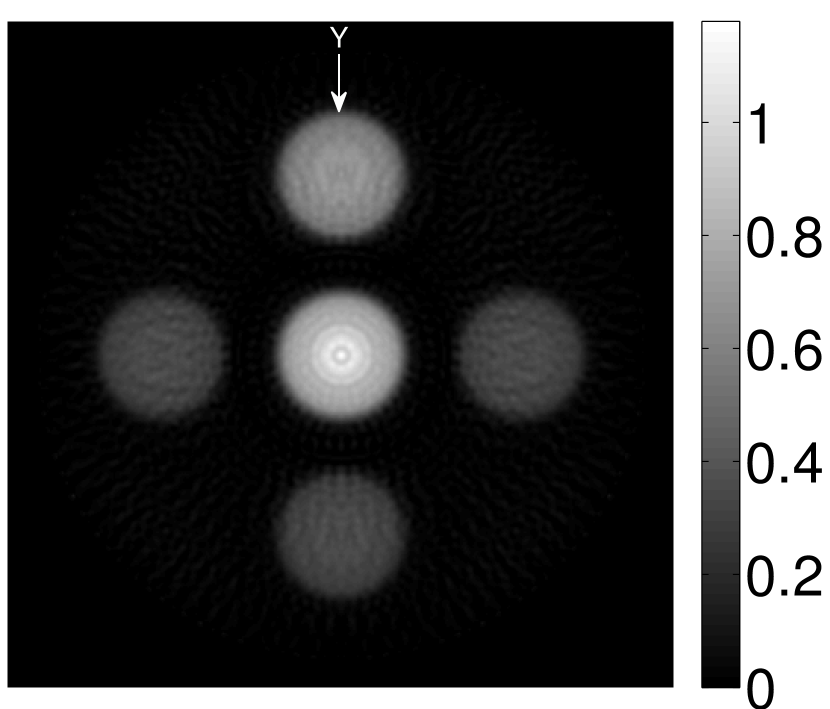

Figure 2(a) shows the image reconstructed by use of the conventional iterative method that utilized a system matrix based on EIR-2. Different values of the regularization parameter from the interval were considered. The reconstructed image with the value of that minimized the RMSE was chosen to represent the best performance of the conventional iterative method. Figure 2(a) and the profile in Figure 2(c) demonstrate that the use of an inaccurate EIR can result in strong artifacts and distortions in images reconstructed by use of the conventional methods.

When the VP algorithm was applied, different values of the regularization parameter from the interval and from the interval were considered. The image that minimized the RMSE was chosen and displayed in Figure 2(b). As revealed by this image and the profiles in 2(c), the VP algorithm yielded an image with fewer artifacts and distortions, and image fidelity was improved as reflected by the reduced RMSE.

Figure 7(a) reveals that use of the inaccurate EIR in the conventional iterative method created strong artifacts and distortions. Figures 7(b) confirms that the artifacts and distortions were significantly mitigated when the VP method was employed. Image profiles for both cases are shown in Figures 7(c). The overall accuracy of the recovered EIR, shown in Figure 7(d) and 7(e), was improved, but it contained spurious oscillations.